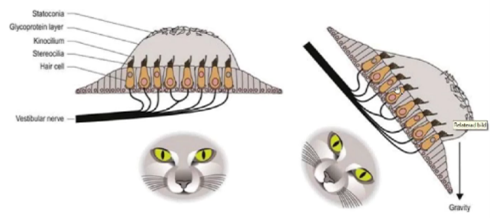

- Kraftningar, lutningar och accelerationer - huvudets position i förhållande till gravitation

- Utriculus

- Sacculus

Vad ansvarar för kraftningar, lutningar och accelerationer - huvudets position i förhållande till gravitation

Utriculus och Sacculus

Vad förmedlar bilden?

Otolitsystemet

- Ovanpå ett gelatinöst lager finns stenar av kalciumkarbonat (dessa kristaller kan lossna), när vi böjer på huvudet kommer dessa stenar dras mot riktningen (enligt bild) varpå hårcellernas stereocilier och kinocilier böjer sig olika mkt beroende på hur de rör sig

- Det nedre örat kommer signalera mera och övre öra mindre varpå signalerna jämförs och lutningen fastställs

Vad detekterar sacculus mer specifikt?

- Mäter rörelse i höjdled (hiss ner eller hopp)